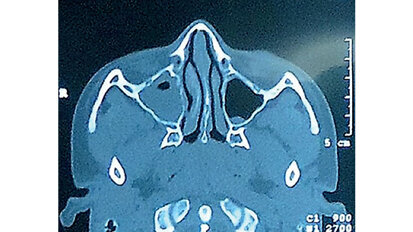

Patologías del seno maxilar

Segundo de una serie de seis artículos. Este artículo es un resumen del capítulo sobre “Patologías del seno maxilar” del libro “Elevación ...

La importancia de la anatomía sinusal

Primero de una serie de seis artículos. Este artículo es un resumen del capítulo sobre “Anatomía sinusal” que aparece en el libro “Elevación ...